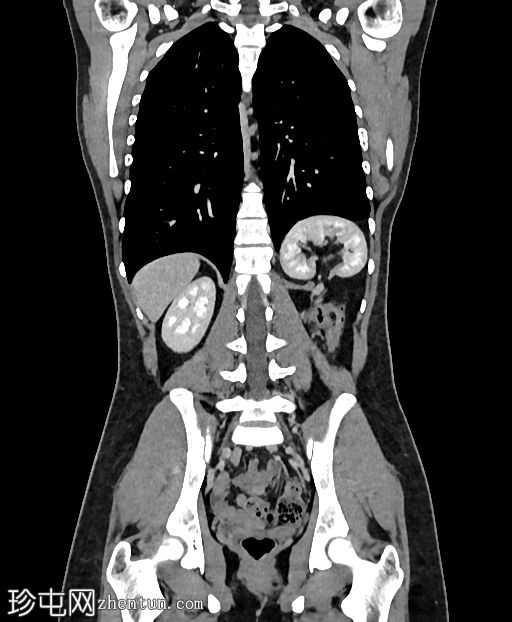

轴位增强扫描

延迟期

左侧Bochdalek疝,大小为8.7 x 7.5 cm,疝颈长3.2 cm。左肾位于胸腔内(Bochdalek疝伴胸内肾),无并发症。左肾旋转不良(过度旋转),肾门朝向后方,肾血管位于后方。肾血管起源正常。肾脏大小为8.6 x 5.8 x 6.1 cm,体积、实质和功能均正常。输尿管膀胱连接处位置正常。未见结石或肾积水。

右肾位置正常,大小正常(头尾径 9.5 cm),肾实质和功能均正常。未见结石或肾积水。